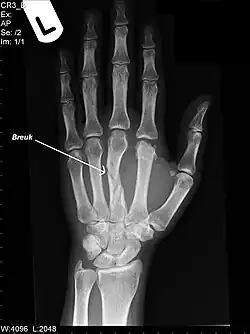

Handsbeenbreuk

Een botbreuk of fractuur is het onderbreken van de continuïteit van het bot. Het kan gaan om een scheur in het bot, maar ook het volledig in stukken gebroken zijn van het bot. Binnen de geneeskunde wordt het #-teken gebruikt als afkorting van fractuur.